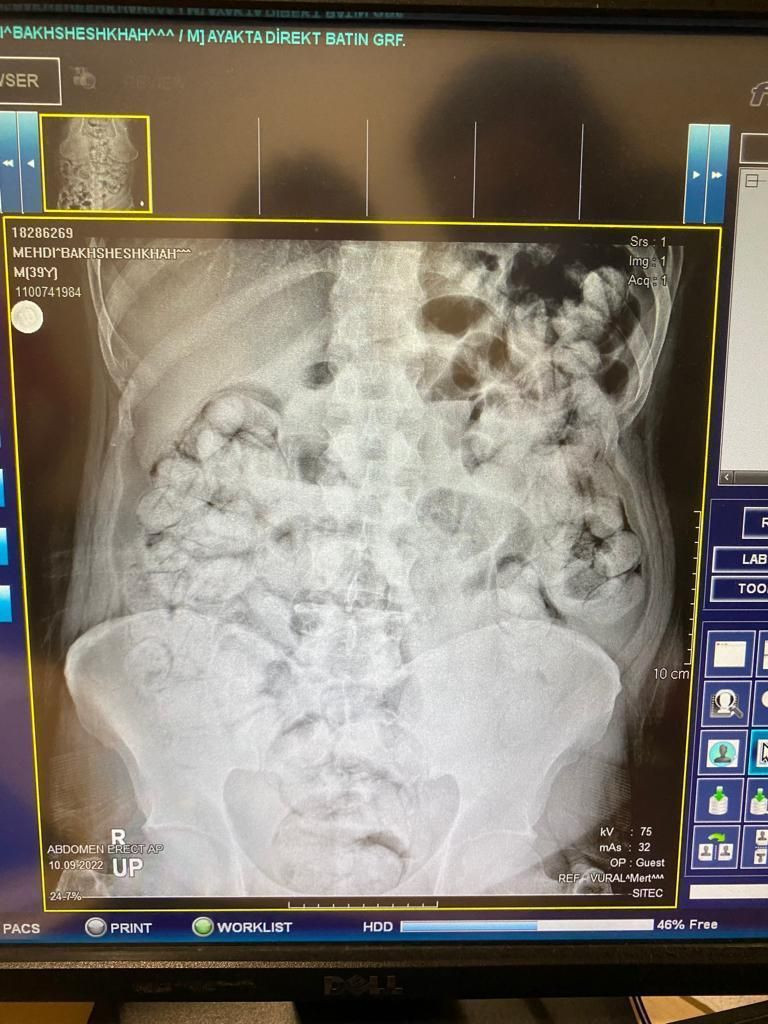

Bir otomobilde durumlarından şüphelenilen ve araçlarında yapılan aramada çantalarından "tokluk hissi veren" ve "bağırsak temizleyici" ilaçlar çıkan İran uyruklu Mehdı B, Mılad F. ve Sıraus G. gözaltına alınarak hastaneye götürüldü.  Çekilen röntgen filmlerinde şüphelilerin vücutlarında 62 kapsül eroin ve 210 kapsül afyon sakızı olduğu tespit edildi.

Röntgen çekimlerinde uyuşturucu kapsüllerinin şüphelilerin neredeyse iç organlarının her tarafına yayıldığı belirlendi. Doktor ve polis, vücutta tek seferde bu kadar yüklü miktarda uyuşturucu görmenin şaşkınlığını yaşadı.